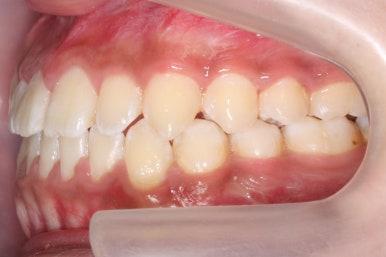

위 사진들은 부산주걱턱교정 키다리아저씨치과에 내원하셨을 당시의 입안 모습입니다.

입 안의 모습에서도 주걱턱의 특징으로는

하악이 앞으로 나와있습니다.

윗니는 뻐드러지고 아래 앞니는 뒤쪽으로 쓰러져 있습니다.

교합이 맞지 않습니다.